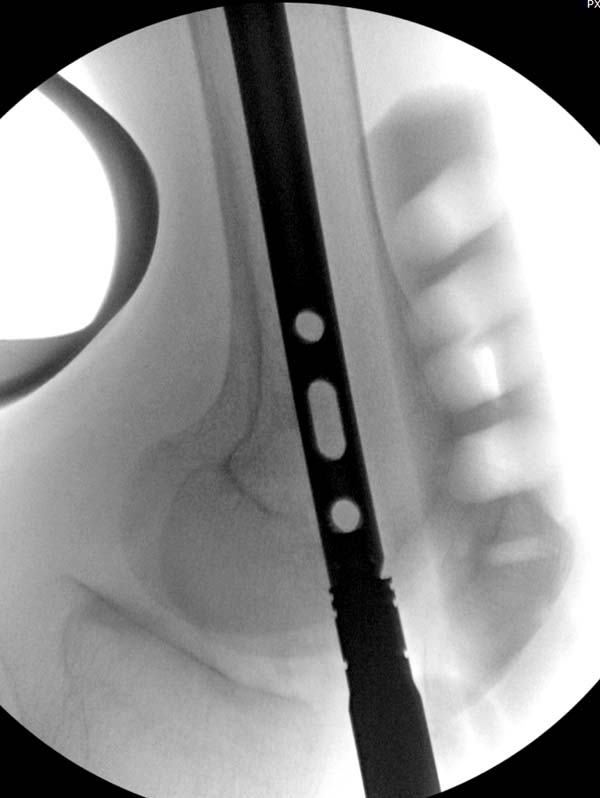

остаться до конца лечения, начал изучать язык... Для облегчения

транспортировки на второй день после поступления правая сторона была

фиксирована ретроградным гвоздем.

Теперь по серьезному. Учитывая качество кости и низкий гемоглобин,

периодический гемодиализ и воодушевленный результатом выступлении

Челнокова, вместо пластины решил попробовать гвоздь. Но жесткие FDА

условии не позволяют воспользоваться дивайсом до получения разрешения на

пользование.

Гвоздь из ретроградного гвоздя DePuy в 15 мм получился немного тоньше,

чем у Российских коллег.

Операция не обошлась без казуса, при подготовке гвоздя произошла ошибка

в расчете. Пришлось коррегигировать по ходу операции, где длинный

дистальный отдел гвоздя срезали во время операции.